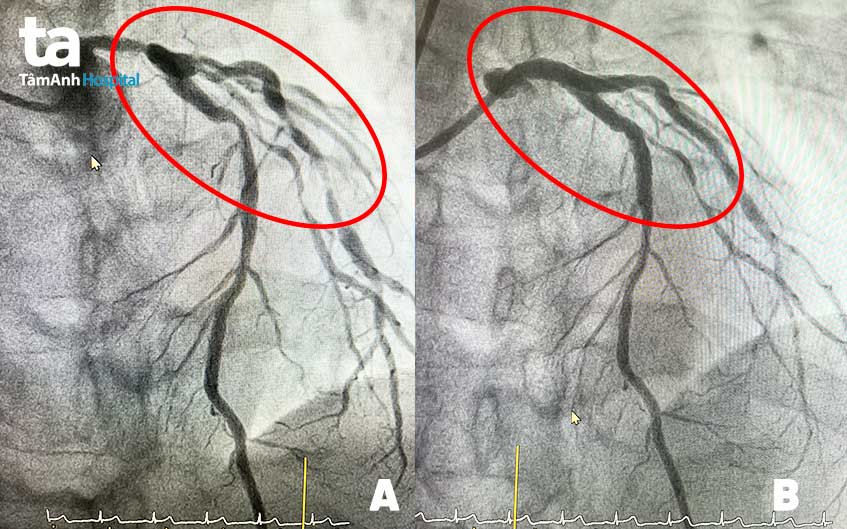

Sau vài ngày uống thuốc theo toa, tình trạng đau ngực không cải thiện, ông Dinh vào TP.HCM thăm khám tại Bệnh viện Đa khoa Tâm Anh. Sau khi siêu âm tim, chụp CT và chụp mạch vành, bác sĩ phát hiện ông bị hẹp nặng thân chung và cả 3 nhánh mạch vành (trên 90%). Ngoài ra, các nhánh mạch máu nuôi tim còn bị vôi hóa rất nhiều. Nếu để thêm một thời gian nữa, “ngã ba” thân chung có nguy cơ tắc hoàn toàn, ngăn máu đến nuôi tim, bệnh nhân lên cơn nhồi máu cơ tim và tử vong trước khi đến viện.

Ca thủ thuật thành công, bệnh nhân được đặt 3 stent đường kính 4.0mm và 1 stent có đường kính 3.5mm ở 2 nhánh mạch vành bên trái. Một tuần sau đó, bác sĩ tiếp tục đặt stent thứ 5 tái thông nhánh mạch vành phải. Kết quả chụp mạch vành kiểm tra sau thủ thuật cho thấy cả 5 stent hoạt động hiệu quả, máu lưu thông tốt, bệnh nhân hết hẳn đau ngực.